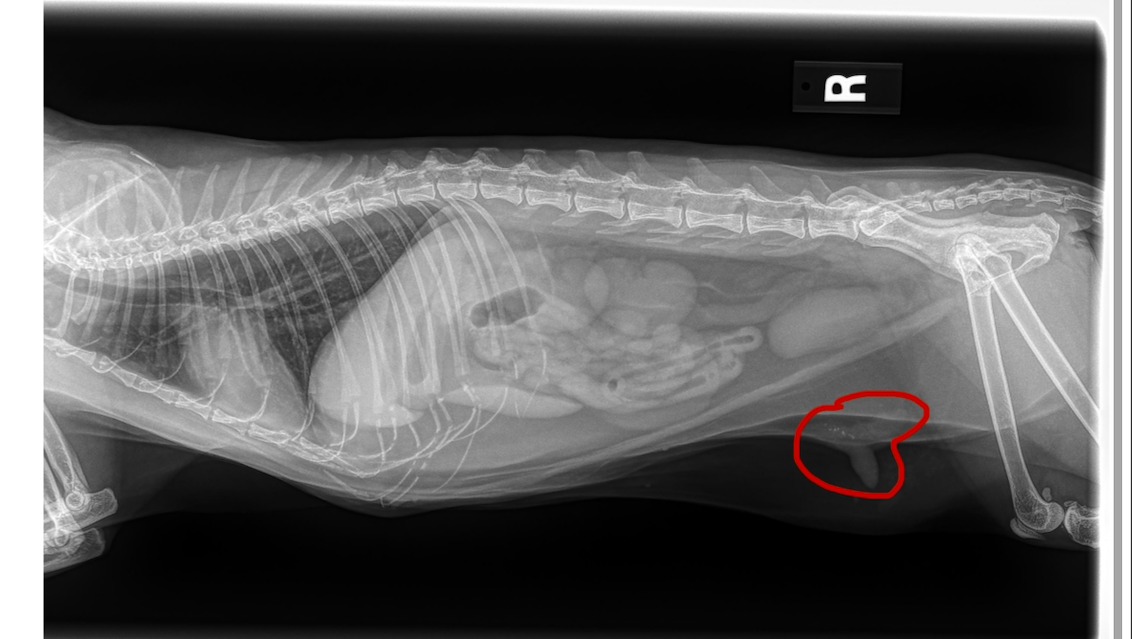

They also discovered a mammary tumor. In cats, these tumors are often aggressive, and the only way to know whether it’s cancer is through surgery and pathology testing. She will need part of her mammary chain removed, followed by biopsy to determine what we are dealing with. Surgery alone is estimated to cost $3,000–$4,500 without complications.

Below is an image of her x-ray, showing the tumor on her belly. Thank you for being here